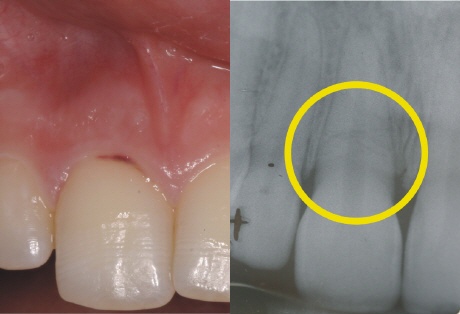

Folge eines Unfalls - Wurzelquerfraktur

Das Röntgenbild zeigt es deutlich als schwarze Linie in der Mitte der Wurzel (gelber Kreis). Der Zahn in der Mitte der Wurzel ist quer gebrochen. Im Mund (links) zeigt sich eine in der Position veränderte Krone (der Mediziner nennt das luxiert), die zudem beweglich ist.